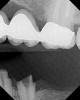

Figure 14  The preoperative radiograph showed an overhanging margin that was in close proximity to the bony crest.

Figure 14